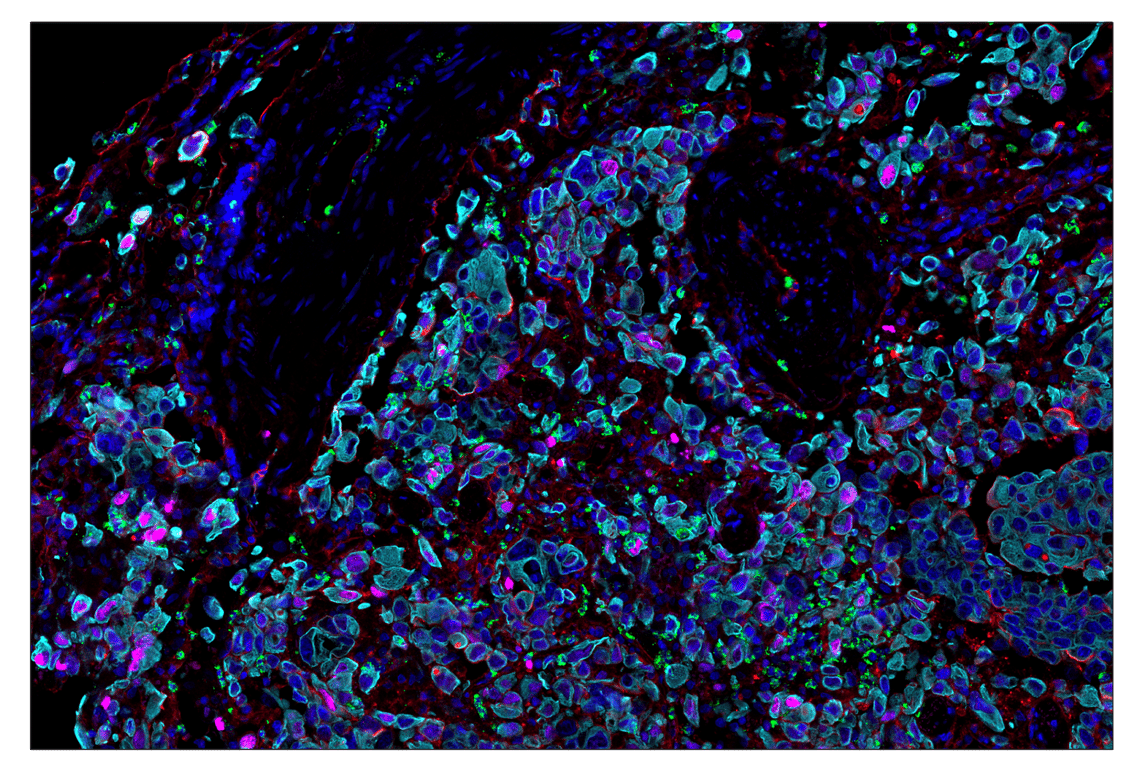

SignalStar multiplex immunohistochemistry (mIHC) is a tool that employs antibodies, oligonucleotides (oligos), and fluorophores to interrogate the cellular presence, location, function, and biomarker co-expression patterns. SignalStar technology enables the detection of multiple phenotypic and functional targets while maintaining spatial context and tissue architecture. These insights are essential for understanding how cells organize and interact to influence the tissue microenvironment and drive disease progression and response to therapy.

The power of the SignalStar system lies in the design of the SignalStar antibodies. These antibodies have been rigorously validated for use in formalin-fixed, paraffin-embedded (FFPE) tissues, and subsequently conjugated to unique oligo tags using site-specific conjugation and thorough purification methodologies. Using a highly specific network of complementary oligos and fluorophores, scientists can amplify the signal for 3-8 targets, even if they are in low abundance.

Figure 1. All antibodies in your plex size of choice (3-8 maximum unique oligo-conjugated antibodies) are added in cocktail in one primary incubation step. Complementary oligos with fluorescent dyes (channels: 488, 594, 647, and 750) amplify the signal of up to 4 oligo-conjugated antibodies in the first round of imaging by building oligo-fluorophore constructs attached to the antibody. If the plex size is greater than 4, the first round of oligos and fluorophores are gently removed, and a second round of amplification is performed to visualize up to 4 additional oligo-conjugated antibodies; the complementary oligo system and the use of the fluorophore removal process enables a second round of antibodies to be amplified from the same substrate, without cross-reactivity. The 2 images are then aligned and fused computationally with either proprietary or open-source software to generate an image consisting of up to 8 targets.

SignalStar™ Multiplex Immunohistochemistry (mIHC) is a technology that employs antibodies, oligonucleotides (oligos), and fluorophores to interrogate cellular presence, location, function, and biomarker co-expression patterns. SignalStar technology enables the detection of multiple phenotypic and functional targets while maintaining spatial context and tissue architecture. These insights are essential for understanding how cells organize and interact to influence the tissue microenvironment and drive disease progression and response to therapy.

The power of the SignalStar system lies in the design of the SignalStar antibodies. These antibodies have been rigorously validated for use in formalin-fixed, paraffin-embedded (FFPE) tissues, and subsequently conjugated to unique oligo tags using site-specific conjugation and thorough purification methodologies. Using a highly specific network of complementary oligos and fluorophores, scientists can amplify the signal for 3-8 targets, even if they are in low abundance.

Figure 1. All antibodies in your plex size of choice (3-8 maximum unique oligo-conjugated antibodies) are added in cocktail in one primary incubation step. Complementary oligos with fluorescent dyes (channels: 488, 594, 647, and 750) amplify the signal of up to 4 oligo-conjugated antibodies in the first round of imaging by building oligo-fluorophore constructs attached to the antibody. If the plex size is greater than 4, the first round of oligos and fluorophores are gently removed, and a second round of amplification is performed to visualize up to 4 additional oligo-conjugated antibodies; the complementary oligo system and the use of the fluorophore removal process enables a second round of antibodies to be amplified from the same substrate, without cross-reactivity. The 2 images are then aligned and fused computationally with either proprietary or open-source software to generate an image consisting of up to 8 targets.